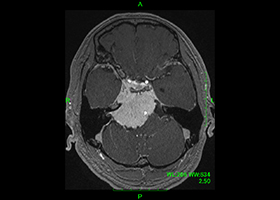

63歳女性、左眼視力低下で発症

[画像所見]

-

右 MRI画像 -

CT画像 左 -

脳血管撮影画像

左眼の奥に大きな動脈瘤認めます。 -

造影三次元CT画像